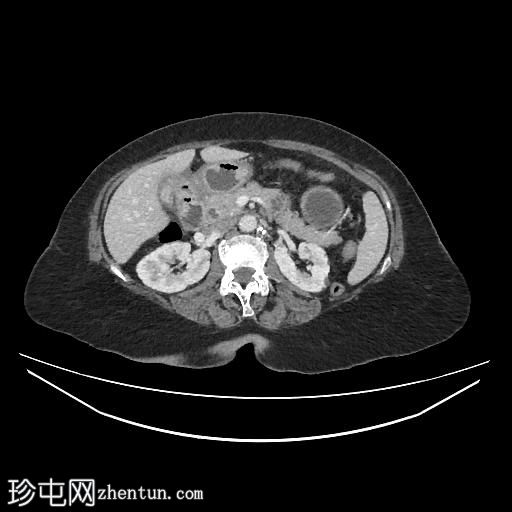

轴位

平扫

胆囊缩小,囊壁增厚,提示慢性炎症改变。胆囊(底部)与十二指肠(球部)腔之间可见细小瘘管,胆囊内及肝内、肝外胆管内均可见气体(胆道积气)。

远端空肠内嵌顿一枚较大的胆结石(3.5 cm),近端空肠袢扩张,回肠袢、末端回肠及结肠均塌陷。